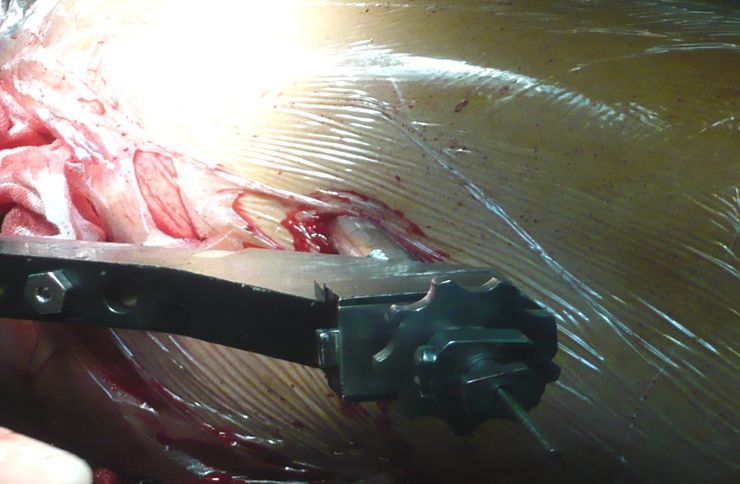

在大转子顶部近端5-8cm处做一长约5cm的切口,在臀中肌筋膜上做一平行切口,沿肌纤维方向分开臀中肌,暴露大转子尖。

置入主钉时,用瞄准器徒手插入,避免暴力锤击,防止骨折移位。

旋紧斜孔保护套使其远端顶住骨皮质以增强保护套筒在操作当中的稳定性。